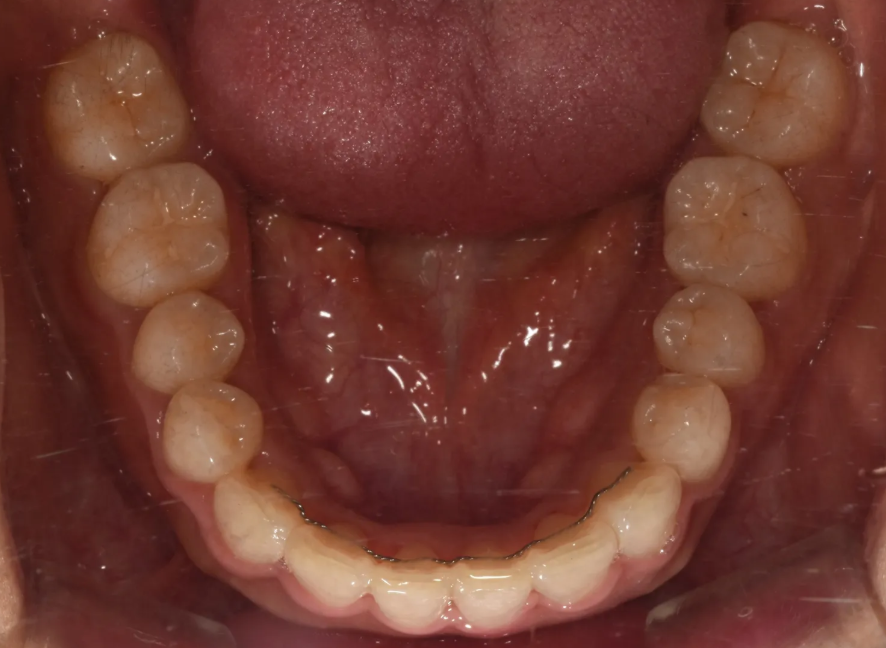

윗니와 아랫니 각각 역시 매우 예쁘게 배열된 모습을 확인하실 수 있습니다.

치료 후 윗니 배열 – 깔끔하게 정리된 모습

아랫니도 역시 고르게 정리되어 있는 모습